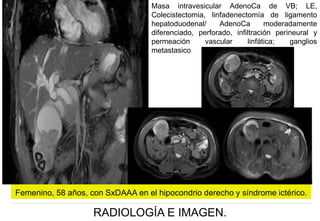

Femenino, 58 años, con SxDAAA en el hipocondrio derecho y sindrome ictérico.

Masa intravesicular AdenoCa de VB; LE,

Femenino, 58 años, con SxDAAA en el hipocondrio derecho y síndrome ictérico.